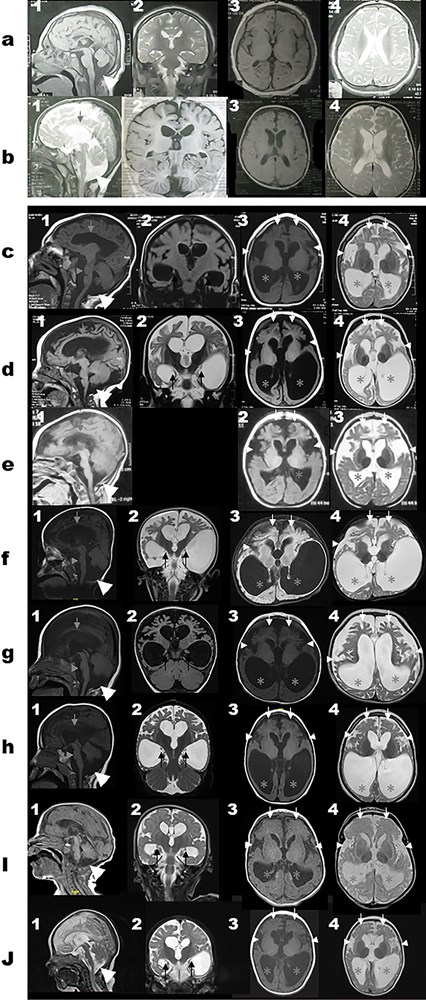

Homozygous pathogenic variants in WDR45B were first identified in six subjects from three unrelated families with global development delay, refractory seizures, spastic quadriplegia, and brain malformations. Since the initial report in 2018, no further cases have been described. In this report, we present 12 additional individuals from seven unrelated families and their clinical, radiological, and molecular findings. Six different variants in WDR45B were identified, five of which are novel. Microcephaly and global developmental delay were observed in all subjects, and seizures and spastic quadriplegia in most. Common findings on brain imaging include cerebral atrophy, ex vacuo ventricular dilatation, brainstem volume loss, and symmetric under-opercularization. El-Hattab-Alkuraya syndrome is associated with a consistent phenotype characterized by early onset cerebral atrophy resulting in microcephaly, developmental delay, spastic quadriplegia, and seizures. The phenotype appears to be more severe among individuals with loss-of-function variants whereas those with missense variants were less severely affected suggesting a potential genotype-phenotype correlation in this disorder. A brain imaging pattern emerges which is consistent among individuals with loss-of-function variants and could potentially alert the neuroradiologists or clinician to consider WDR45B-related El-Hattab-Alkuraya syndrome.